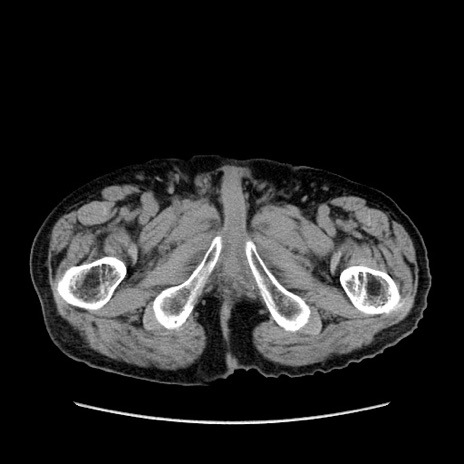

症例24(横断像)

【症例】80歳代男性

【主訴】左側腹部痛、嘔吐

【現病歴】本日早朝より左腹部に痛みあり。昼頃嘔吐認めたため、救急要請。

【既往歴】直腸癌(Mile手術)、胆摘

【身体所見】意識清明、BT 35.9℃、BP 221/93mmHg、SpO2 97%(RA) 、腹部:左ストーマ周囲に限局性の腹部膨隆あり。 膨隆部自発痛・圧痛あり・軟。

【データ】WBC 7700、CRP 0.09